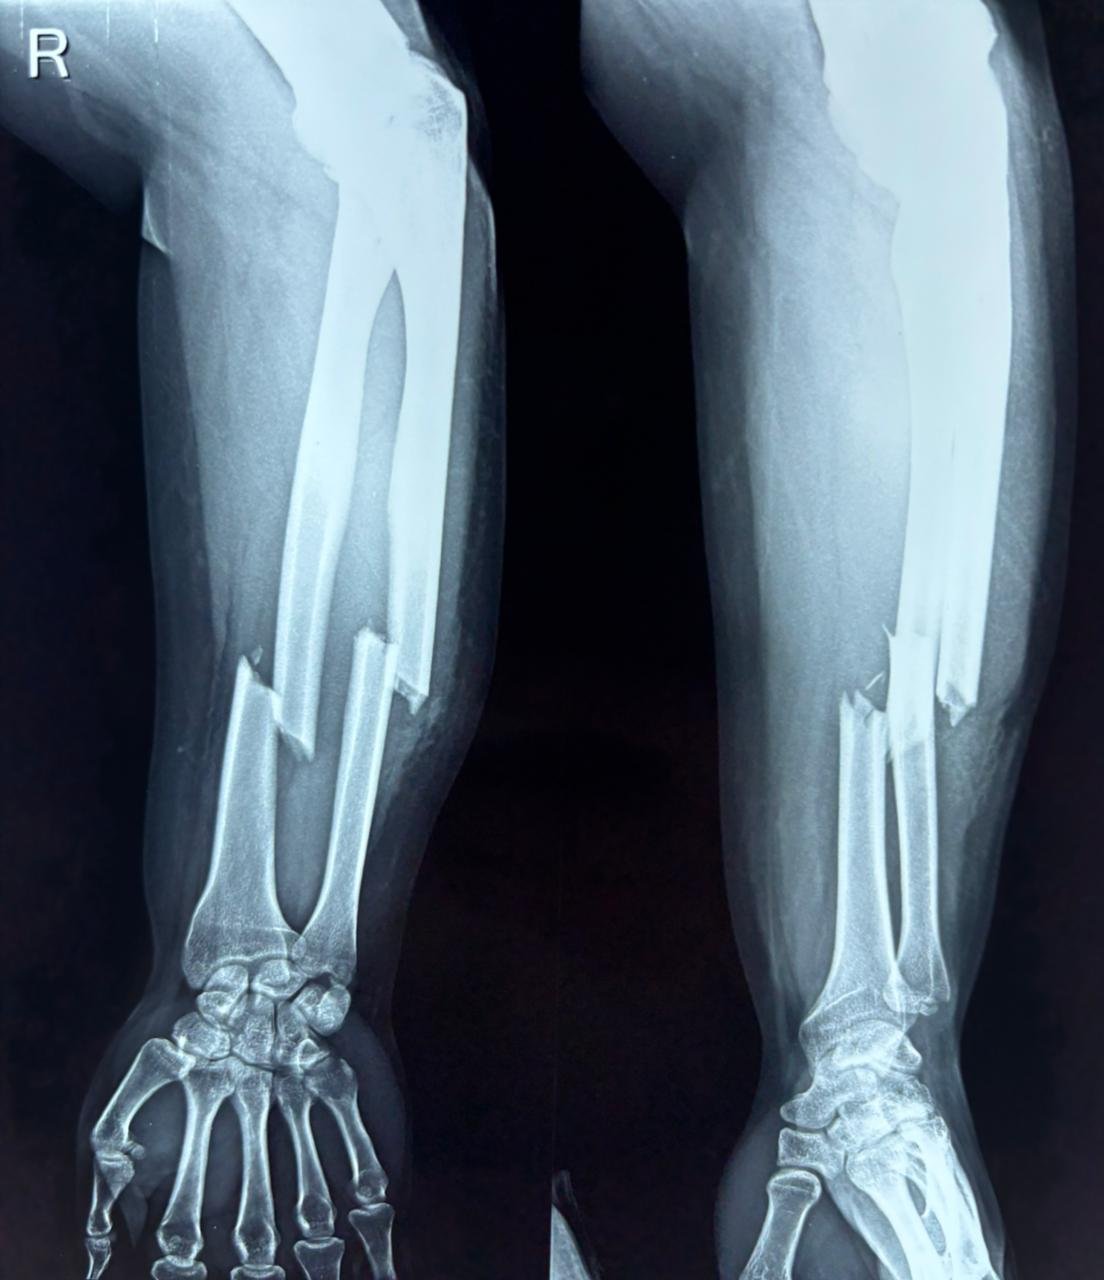

Both Bones Forearm Fracture

Atlas ID: 3 • Orthonotes Atlas

Both Bone Forearm Fractures

Both Bones Forearm Fracture - Case Based Disucssion

Both Bones Forearm Fracture. Orthonotes Atlas. The Bone Stories. Available at: https://orthonotes.in/atlas/both-bones-forearm-fracture-69b94a9c3a62f Accessed: 2026